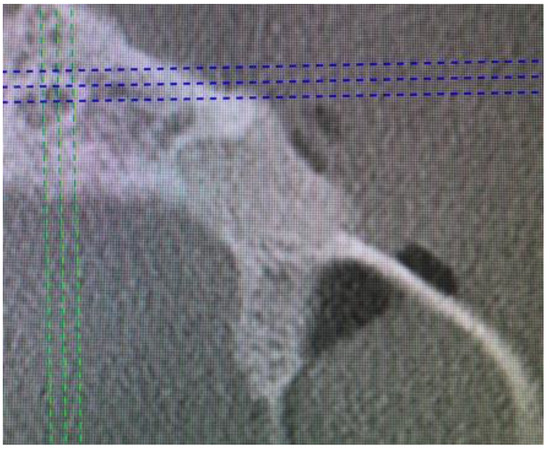

Cone beam computed tomography (CBCT) evaluation revealed the perforation of the buccal cortical bone plate, with expansion towards soft tissues, measuring about 6 mm at longest diameter (Figure 3 and Figure 4). Palatal bone plate remained without any lesions. Because of close proximity to the apex of first premolar and scheduled enucleation with bone curettage/drilling, a decision of endodontic treatment 24 was scheduled. Secondly, such treatment was also indicated because of (1) the loss of cortical plane (possible local aggressiveness of lesion), (2) possible GOC/BOC or other dental-related cyst/tumor occurrence; (3) possible teeth pulp necrosis/inflammation after extensive curettage/bone drilling used for local radicalization protocol; (4) minimizing the time needed for secondary surgery if such would be necessary in case of other pathology. On CBCT further evaluation, a slight sclerotic border close to both tooth apex/roots was visible. Teeth structure remained preserved, with only the buccal cortical bone perforation. On the floor of the left maxillary sinus, a retention mucous cyst was seen; however, due to the clinical irrelevance, only a laryngologist consultation was scheduled.

Figure 6. CBCT sagittal view after surgery.